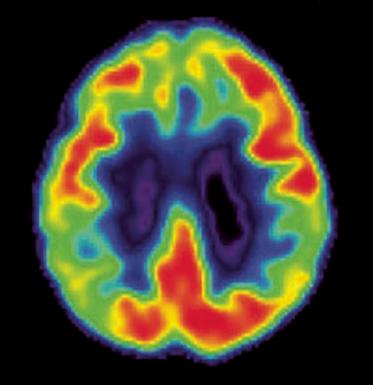

• Brain changes that occur with AD.

• Risk factors for AD.